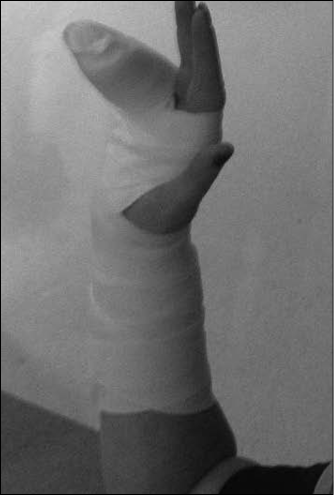

If one or more of the above four tests are positive, radiographs should be obtained with navicular views and the wrist should be treated empirically for a scaphoid fracture. Many authors advocate the use of a long-arm thumb spica cast for immobilization of scaphoid fractures to prevent pronation and supination of the hand. A cast or splint used for a scaphoid fracture must hold the hand radially deviated, or at least in a neutral position. A short-arm thumb spica splint may be used for suspected scaphoid fractures. (See Figure 3.) Any ulnar deviation will cause separation of fracture fragments as strain is placed across the scaphoid, and prevent proper healing.

Figure 3. Thumb Spica Splint